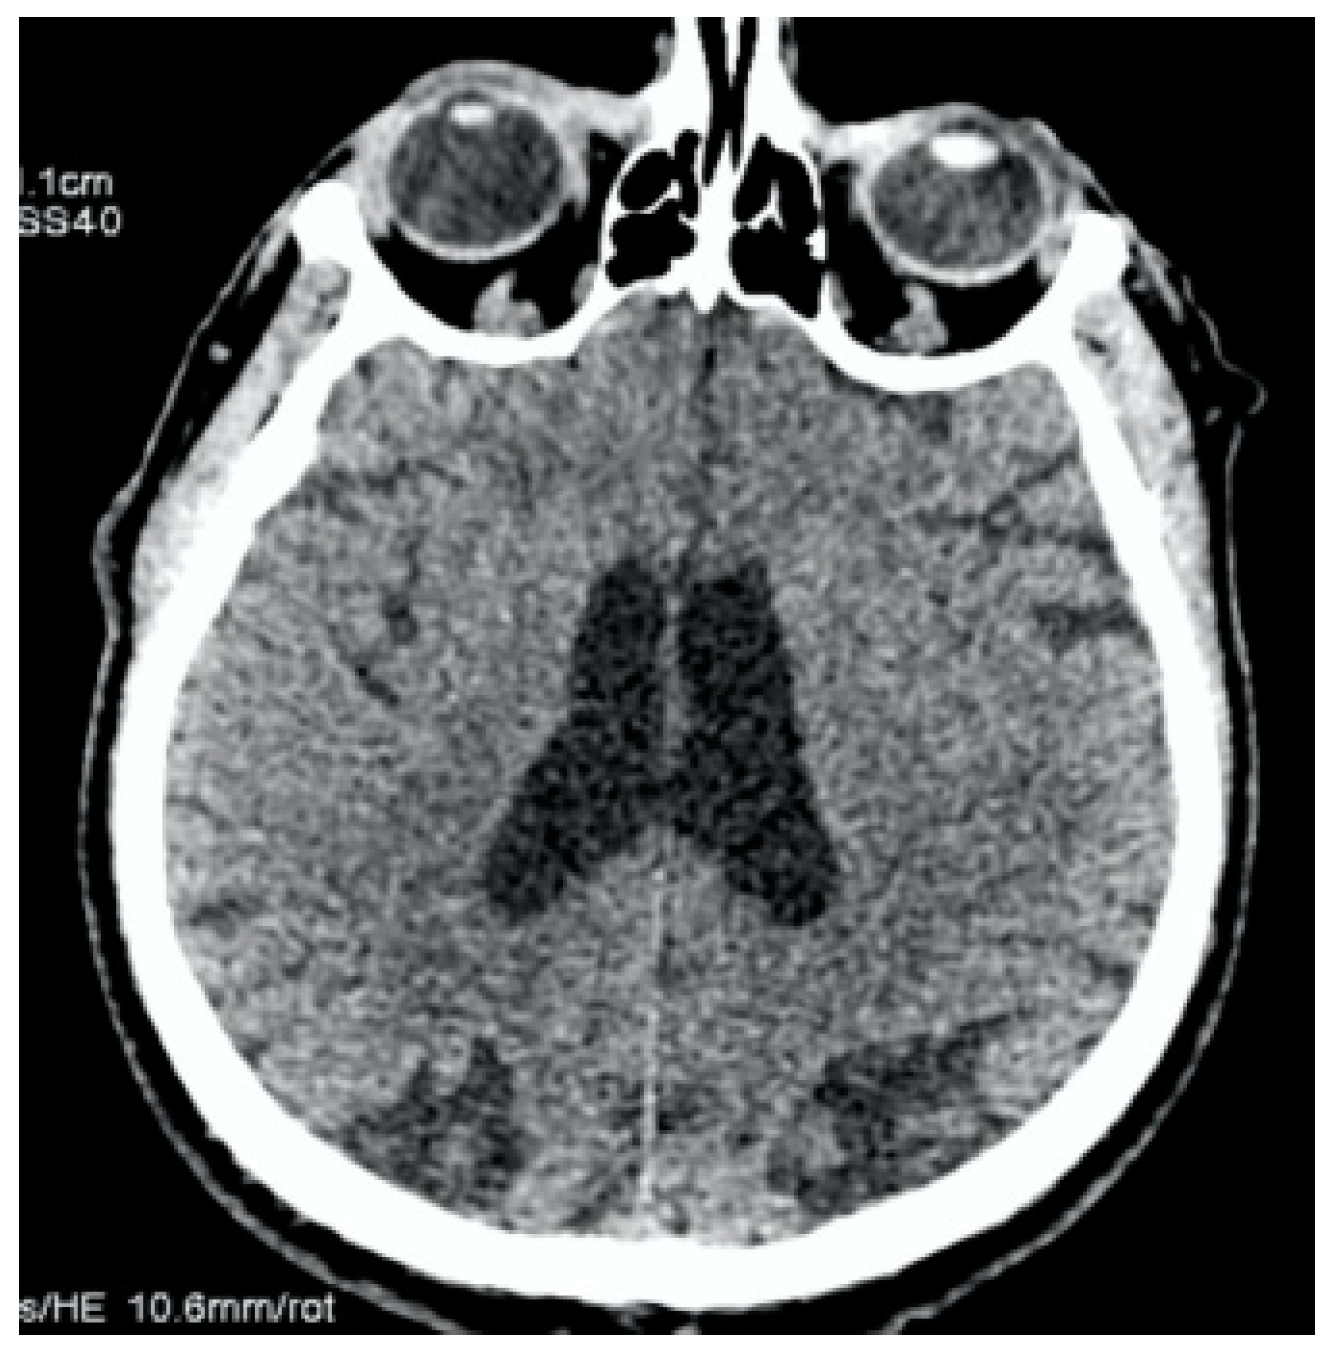

The antibiotic therapy was prescribed by the next scheme: Vancomycin 1 g taken 2 times per day and Gentamicin 80 mg taken 3 times per day, as well as symptomatic treatment. In the next two weeks, the patient noted an improvement and the temperature normalized. However, on the day of discharge, in the presence of medical personnel, the patient developed generalized convulsive syndrome, stopped by intravenous diazepam administration and complicated by left-sided hemiplegia. Immediately, the MSCT was performed. There were no signs of stroke, ASPECTS = 10 (Figure 3).

Figure 3.

Clinical Case 1, Patient M., 73 years old. Brain MSCT in 20 min after symptoms’ onset. No data for ischemia or brain damage; ASPECTS = 10.